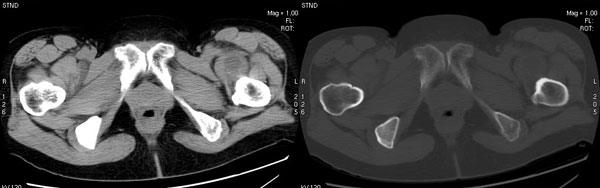

以下是引用jiajie在2006-7-14 17:19:00的发言:[br]ct所见:双侧髋关节不对称,左侧关节间隙变窄,关节面毛糙。左侧股骨头变形、无明显变小,前上缘与髋臼融合,融合处骨质明显增生硬化,并见数个小囊变影。股骨头下端与股骨颈交界部见囊样变,邻近肌肉内见囊样密度减低区,ct值24hu。右侧髋关节形态未见异常。[br][br]ct诊断:左侧髋关节结核可能,请结合临床资料进一步分析。

以下是引用lihuuuu在2006-12-5 10:14:00的发言:[br]定位像示:左侧髋臼变浅,倾斜度加大,髋臼外上缘呈波浪状不规则,骨质增生硬化,髋关节上缘间隙明显变窄,股骨头向外上轻度移位。轴位像示:左侧股骨头变形,前上缘与髋臼融合,融合处骨质明显增生硬化,并见数个小囊变影。股骨头下端与股骨颈交界部见囊样变,邻近肌肉内见密度减低区,ct值24hu,内缘见弧形高密度钙化影。右侧髋关节形态未见异常。[br]ct诊断:左侧髋臼发育不良[br] 左侧股骨头缺血性坏死[br] 左侧肌肉内低密度影伴有高密度钙化-考虑早期骨化性肌炎[br] [br]“我认为在描述上已经写了肌肉部分,印象诊断里应该写主见”[br]